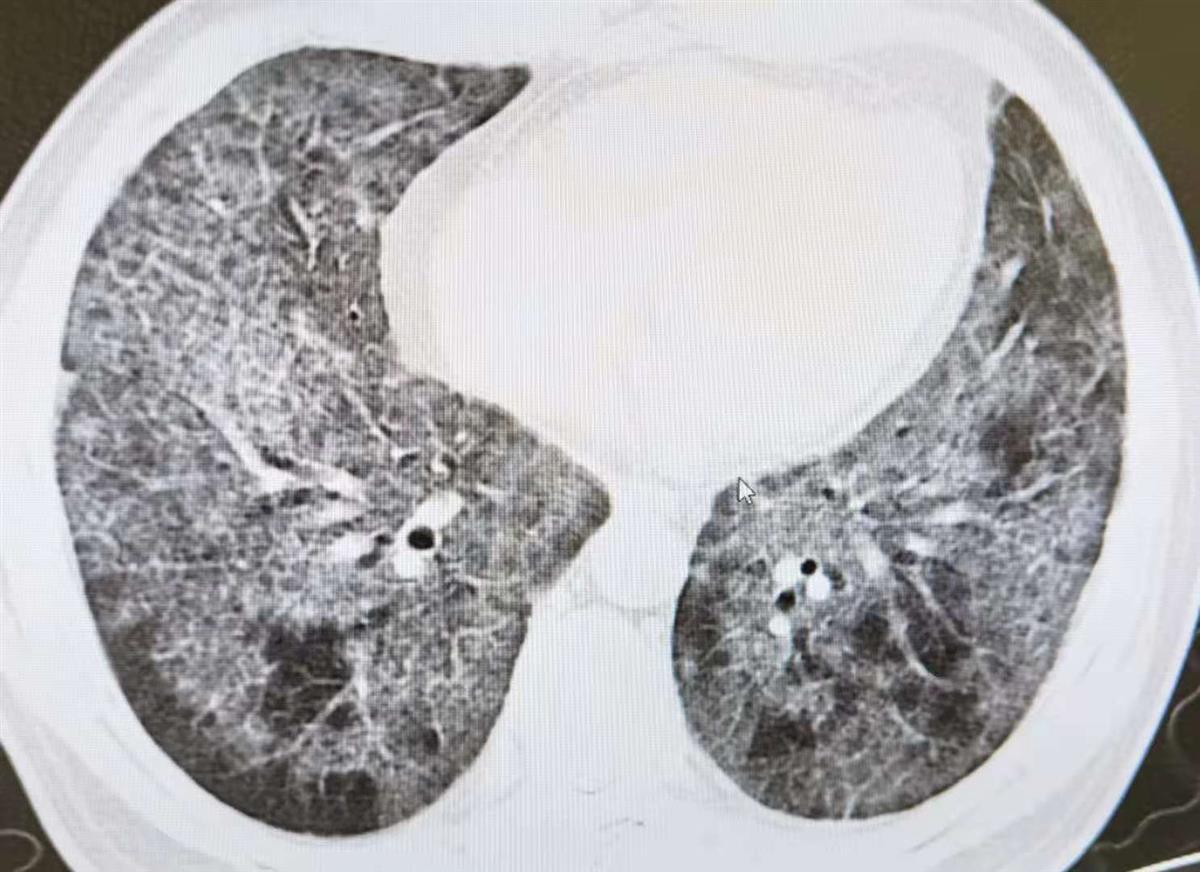

没想到,吴先生气喘、胸闷症状逐渐加重, 7月底,他来到武汉市泰康同济医院健康管理中心体检,胸部CT检查提示,双肺弥漫性间质性炎症改变,呈地图状、铺路石状分布。当即,该中心开通绿色通道,带吴先生转至门诊就诊。

吴先生肺部CT影像

该院呼吸与危重症医学科主任刘勇谋检查发现,吴先生双手手指明显是杵状指,在不吸氧状态下,脉搏血氧饱和度仅85%,专家向患者交代病情后立即将他收入院。在完善相关检查中, 8月6日进行支气管镜检查,肺泡灌洗液及刷片检查PAS染色均为阳性,结合病史及影像学特征,最终诊断为“肺泡蛋白沉积症”。